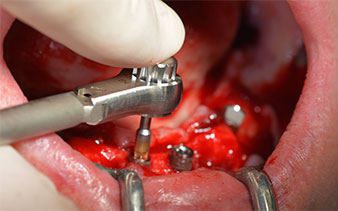

The surgical protocol for the implants employed (SKY, bredent medical) specifies a speed of 1,200 rpm for the pilot drilling (Fig. 7 - 9).